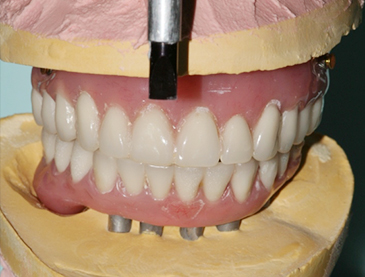

Fully edentulous clinical cases